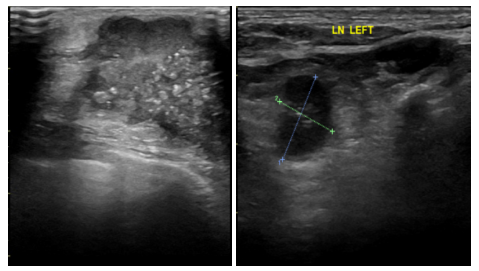

2021-6-9乳腺及腋窝淋巴结超声:左侧乳腺外上象限见大小约45*21mm低回声团块,边界不清,形态不规则,肿块前缘达皮肤层,内回声不均匀,内见多枚杂乱强光点,可见血流信号,测其动脉血流RI0.76。余双侧乳腺腺体形态、结构未见异常。左侧腋窝见多枚低回声结节,边界清,形态饱满,有包膜,内见多发强光点,较大者约13*10mm,内可见血流信号。右侧腋窝未见肿大淋巴结回声。

影像诊断:左侧乳腺低回声团块(BI-RADS:5类,考虑浸润性Ca);左侧腋窝多发异常肿大淋巴结。

图1.乳腺B超(2021-6-9)